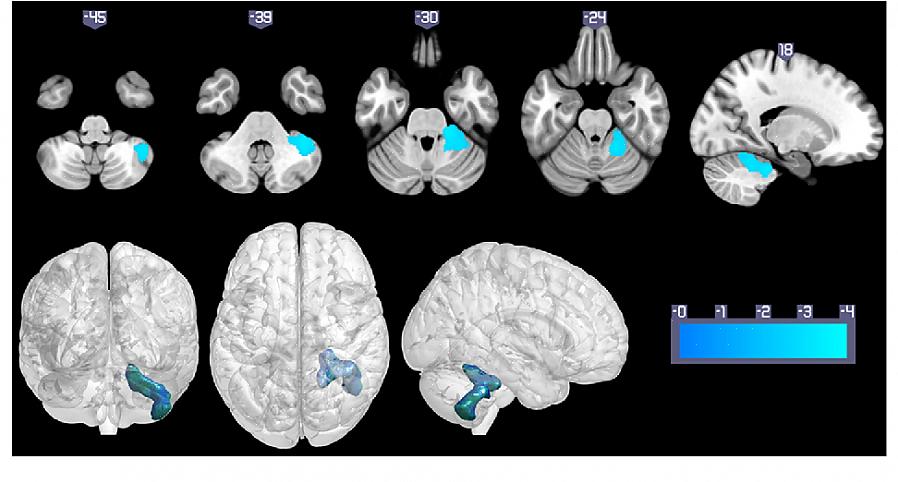

בנוסף לכך, העלייה ב-VHR הקשורה לוויסות רגשי מלווה בשינויים בזרימת הדם למוח. זה קורה באזורים שזוהו כחשובים לוויסות רגשי ולתהליכים מעכבים.